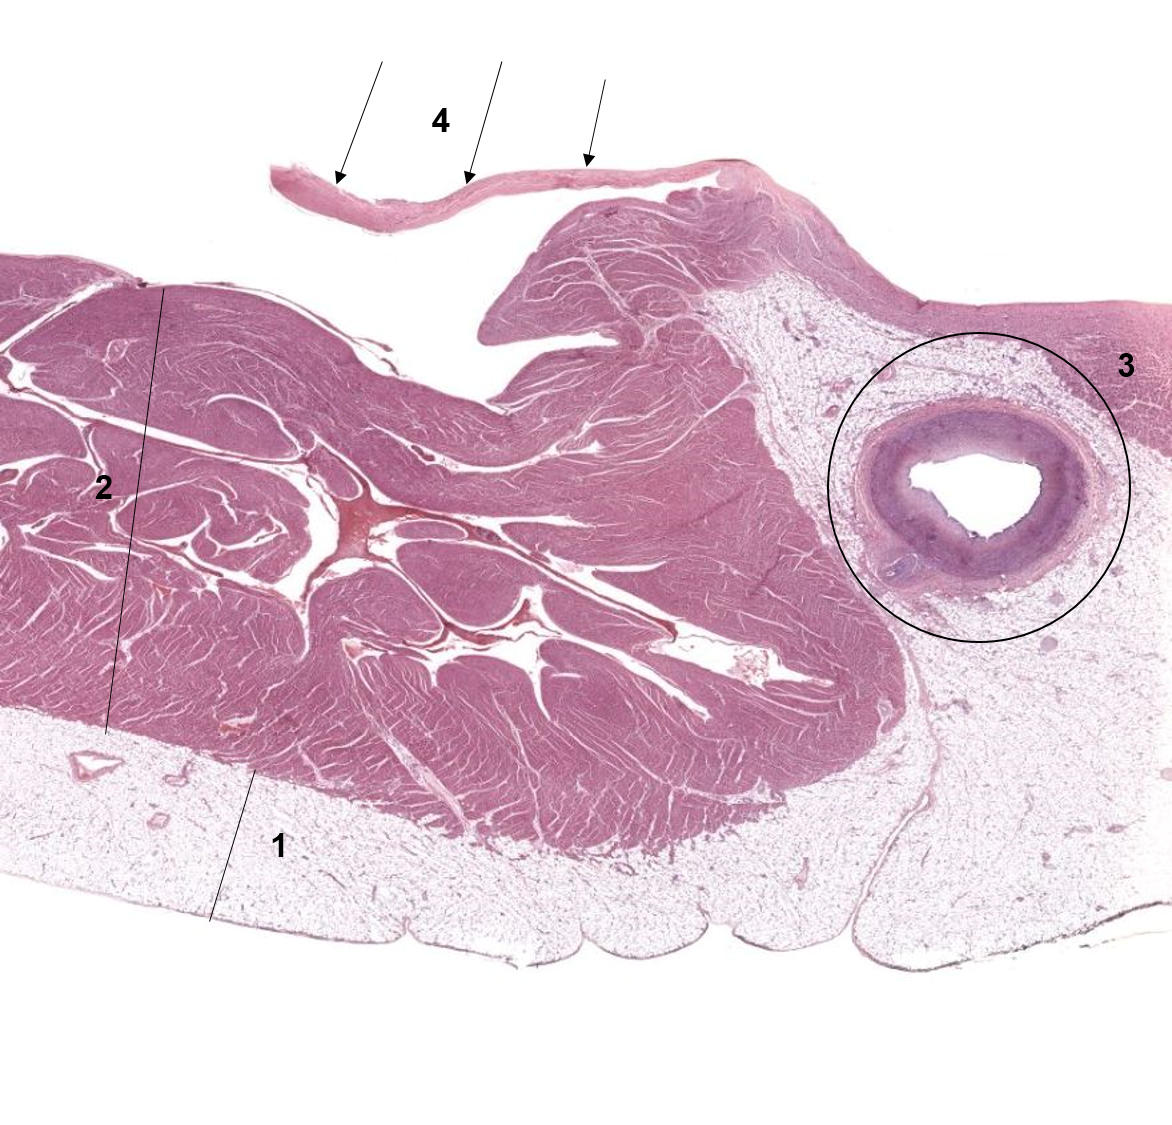

1: Epicárdio

2: Miocárdio

3: Artéria coronária

4: Válvula